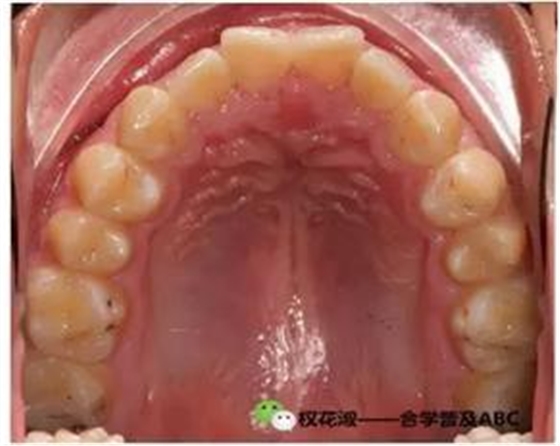

下面是理想合的幾張圖片:

大家在沒事的時(shí)候可以仔細(xì)琢磨這張幻燈,關(guān)于前后牙牙齒的覆合覆蓋,中線關(guān)系,牙齒的排列等等。其實(shí)這張幻燈對我們理解上下牙齒的咬合也是非常有幫幫助的。大家看右下的照片詮釋的是尖牙保護(hù)合的概念。

這張照片就是咬合的照片,也是讓大家加深牙齒形態(tài)完整性這方面的概念,也就是說如果想要保證穩(wěn)定的咬合關(guān)系,牙齒無磨耗是十分關(guān)鍵的。